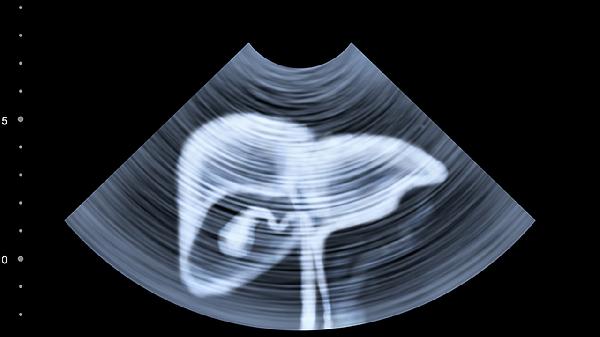

随着肝内包虫囊肿生长,患者可在右肋缘下触及质地坚韧、表面光滑的肿块。囊肿体积较大时可导致局部隆起,按压有弹性感。需注意与肝脏肿瘤鉴别,超声检查可见特征性双壁征或囊内子囊结构。